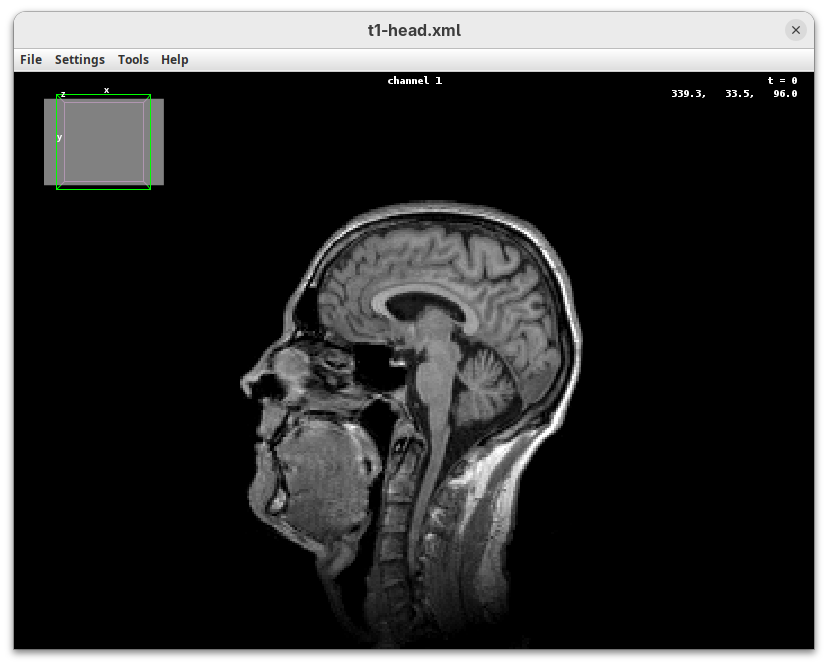

BigDataViewer

BigDataViewer (Pietzsch et al. 2015) is one of the most important tools for visualizing large, multidimensional datasets. It provides a simple and intuitive interface and shortcuts to swiftly navigate through your sample even on a regular laptop. This is possible because of the underlying file format used by BigDataViewer: the XML/HDF5 combo. Therefore, before opening the plugin, we must convert our dataset.

The XML file stores metadata information about the image. The HDF5 file stores actual image data. These two files will always be in a pair. To open the XML/HDF5:

- Go to

Plugins>BigDataViewer>Open XML/HDF5and select thet1-head.xml.

The BigDataViewer interface will open showing an optical section of the head sample.

Getting familiar with BigDataViewer is an essential skill for navigating large 3D datasets. It’ll also be important for the multiview registration pipeline. So, take the time to learn the basic commands and shortcuts. It is nicely intuitive. The BigDataViewer’s page on the ImageJ Docs has the official documentation and we can also go to Help > Show Help for an up-to-date overview.

Some of the movements to try:

Left-click and drag: turn the sample around the mouse pointer at any arbitrary angle.Right-click and drag: move the sample in the XY plane (of the view).Scroll: move through the Z plane (of the view). UseShift+Scrollto move fast.Ctrl+Shift+Scroll: zoom in or out.

But, most importantly, are the commands to put your sample back to its original orientation or along any of the original dimension axes:

Shift+Z: orient the sample on the XY plane.Shift+X: orient the sample on the ZY plane.Shift+Y: orient the sample on the ZX plane.

Finally, a visual tip. The default interpolation between image slices is nearest-neighbors. Press I to activate the tri-linear interpolation to obtain a much smoother (and improved) data visualization.